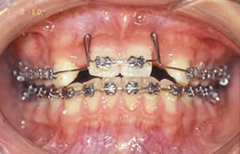

先欠(生まれつき歯がない)状態を矯正治療とインプラントで治療した症例

矯正で歯列を整え、先欠部にインプラントを埋入しセラミックの歯を入れて仕上げたケース。

約20年経過後も問題はございません。